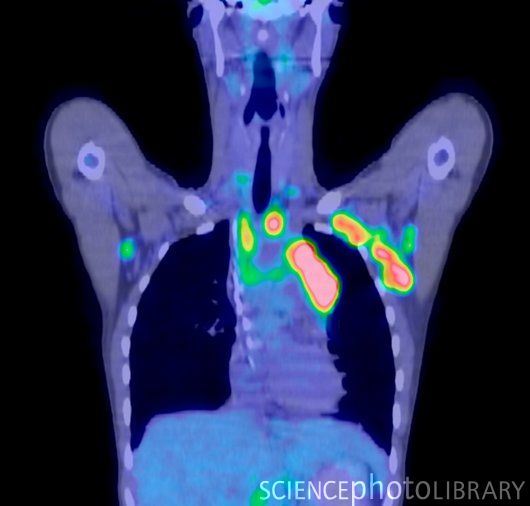

Диагностика лимфомы Ходжкина с помощью ПЭТ и КТ